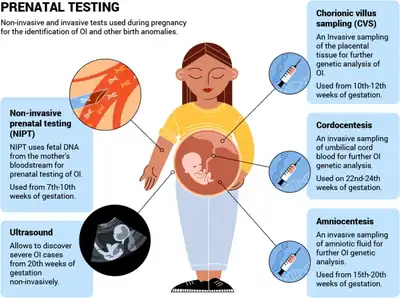

Diagnosis is typically based on medical imaging, including plain X-rays, and symptoms. Signs on medical imaging include abnormalities in all extremeties and the spine.[49] An OI diagnosis can be confirmed through DNA or collagen testing, but in many cases, the occurrence of bone fractures with little trauma and the presence of other clinical features such as blue sclera are sufficient for a diagnosis. A skin biopsy can be performed to determine the structure and quantity of type I collagen. DNA testing can confirm the diagnosis, however, it cannot exclude it because not all mutations causing OI are known and/or tested for. OI type II is often diagnosed by ultrasound during pregnancy, where already multiple fractures and other characteristic features may be present. Relative to control, OI cortical bone shows increased porosity, canal diameter, and connectivity in micro-computed tomography.[50] Severe types of OI can usually be detected before birth by using an in-vitro genetic testing technique.[51]

Genetic testing

In order to determine whether osteogenesis imperfecta is present, genetic sequencing of the COL1A1, COL1A2, and IFITM5 genes may be done.[53][54]

Duplication and deletion testing is also suggested to parents who suspect their child has OI.[53]

The presence of frameshift mutations caused by duplications and deletions is generally the cause of increased severity within the disease.[53]